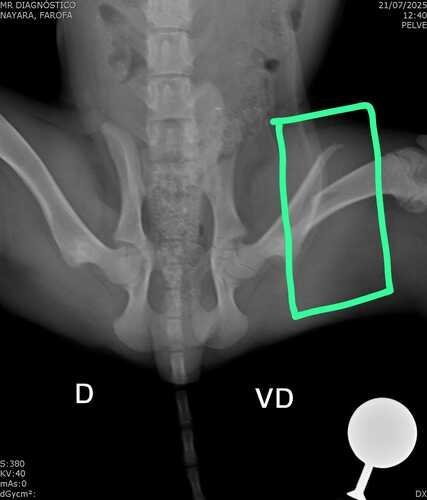

O Farofa foi atropelado e resgatado dia 19/07/2025 no st. Dona Iris 1, Trindade - GO. Ele é um filhote de aproximadamente 4 meses que foi atropelado e quebrou o fêmur.

Testes para cinomose e doença do carrapato negativos, porém, apresenta quadro de anemia, além de estar muito magro. Ele foi internado no Centro Médico Veterinário Bicho Mimado, st. Jardim América, Goiânia/GO. Até o momento, gastei R$ 1914,10 , contudo, não tenho condições financeiras de arcar com os custos da cirurgia.

Em anexo segue foto do farofa, foto e laudo do RaioX, comprovantes de pagamentos da clínica (consulta, exames de sangue, teste de cinomose, medicações, RaioX, sedação para realizar o RaioX e ultrassom), comprovante de transferência das internações, comprovante de pagamento de ração, simparic e patê, comprovante de transferência dos medicamentos para ser cuidado em casa.